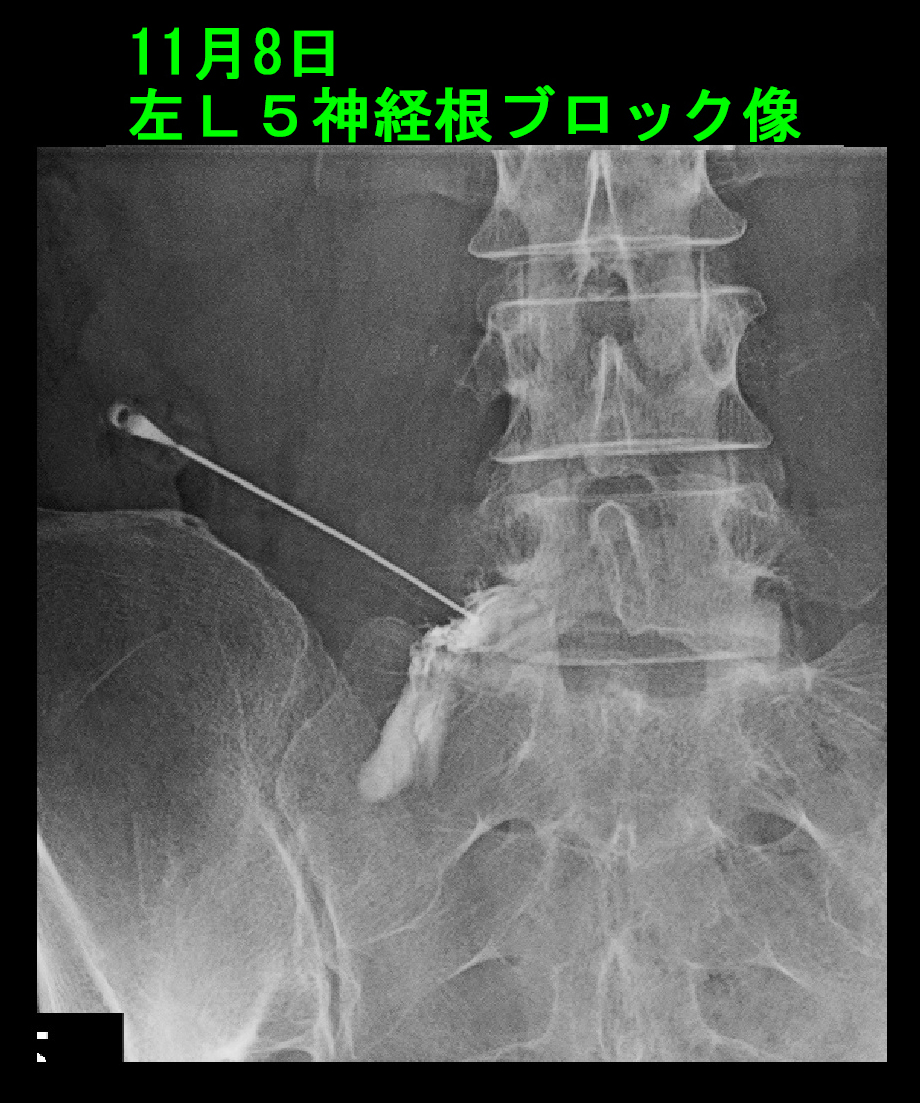

2日後の11月8日にYさんは受診されました。VAS8→5という評価でしたが、痛みが強いので早期の診察を希望されたとのことでした。右下腿から足の外側の痛みで夜間どうしていいか分からないとも述べていました。

L5SがYさんの病因ではないと判断するべき経過です。また、MRI画像の見直しです。